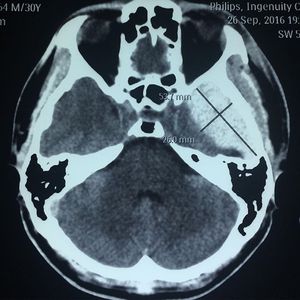

An epidural hematoma on left parietobasal region...